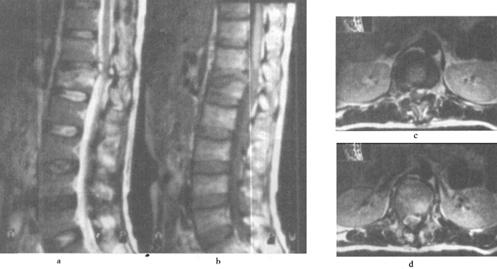

(2)出血:包括脊髓内出血和硬膜外血肿(图7-14至图7-16)、硬膜下出血和蛛网膜下腔出血等。脊髓内出血是不可逆损伤,其信号改变随时间变化较大。急性期(24h内)髓内出血灶在T1WI呈中等信号或不均匀信号,在T2WI呈中央低信号出血灶,外围水肿为高信号。亚急性期(3~5d)血肿在T1WI信号逐渐升高,在T2WI信号仍较低,慢性期血肿在T1WI和T2WI均为高信号。脊髓硬膜外血肿、硬膜下出血和蛛网膜下腔出血,在MRI上表现为椎管内脊髓外的软组织增厚影,在T1WI呈不均匀低信号,在T2WI为高信号。硬膜外出血脊髓受压移位明显。

图7-15 颈髓挫裂伤:T1W(a)T2W(b)矢状面,脊髓增粒为髓水肿所致,T1W和T2W信号增高。横断面(c)脊髓内可见斑片状出血灶,硬膜外血肿T2W亦呈高信号,脊髓压迫向右后移位。颈后方软组织出血水肿,在T2W亦为高信号

图7-16 L1压缩骨折,脊髓挫裂伤:T1W(a)和T2W(b)矢状面,L1椎体呈楔状变形,椎体骨折,但无移位。后方硬膜外及脊髓内可见高信号血肿,在横断位T1W(c)、T2W(d)成像,如箭头所示脊髓圆锥内椭圆型高信号影,为出血所致。椎体骨髓水肿及出血。

(3)脊髓挫伤:脊髓挫伤是脊髓水肿伴局灶性出血,在T1WI小的出血灶可呈高信号,邻近水肿为等低信号,T2WI呈混杂高信号(图7-16)。